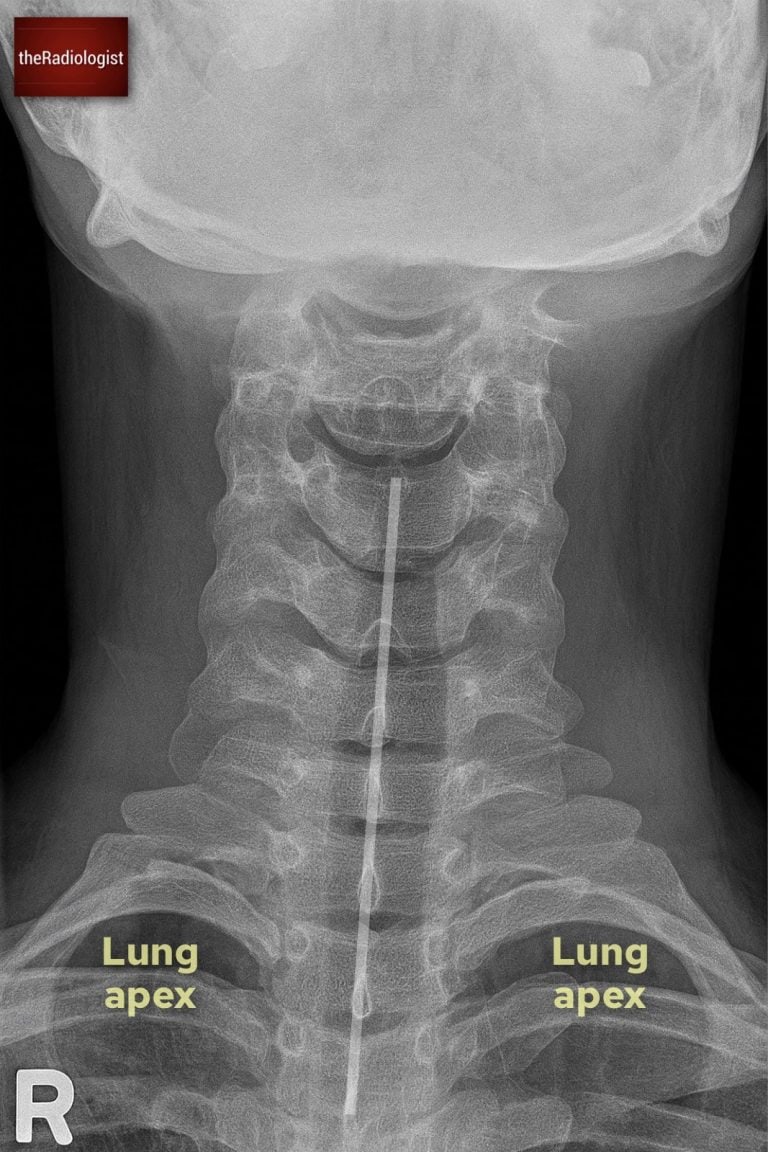

Long AP view review

The long AP cervical spine view complements the lateral and peg projections by allowing assessment of the spinous processes and interspinous spacing. Although less sensitive for fractures than the lateral film, it provides an important check for alignment and helps detect rotational or unilateral facet injuries.

Annotated view of a long AP view

1. Film adequacy

Confirm that the film is centred and includes the cervical spine down to the cervicothoracic junction. The spinous processes should be clearly visible in the midline without significant overlap from the mandible or shoulders.

2. Spinous process alignment

The spinous processes should form a straight vertical line in the midline of the film. Any deviation away from this line may indicate rotation, malalignment, or more importantly, a unilateral facet joint dislocation. Even subtle offset should prompt careful reassessment with the lateral view or CT.

Beware of pitfalls: bifid spinous processes can create the illusion of misalignment, so this variant should not be mistaken for pathology.

3. Interspinous distance

Next, assess the spacing between adjacent spinous processes. These distances should be roughly equal throughout the cervical spine. A gap that is more than 50% wider than the one above or below is abnormal and strongly suggests anterior dislocation or posterior ligamentous injury.

Watch out if the neck is held in flexion due to spasm or positioning: the interspinous distances may appear falsely widened.

4. Lung apices

The AP view normally gives you a good view of the lung apices so ensure you don’t miss a pneumothorax, incidental Pancoast tumour or rib fracture.